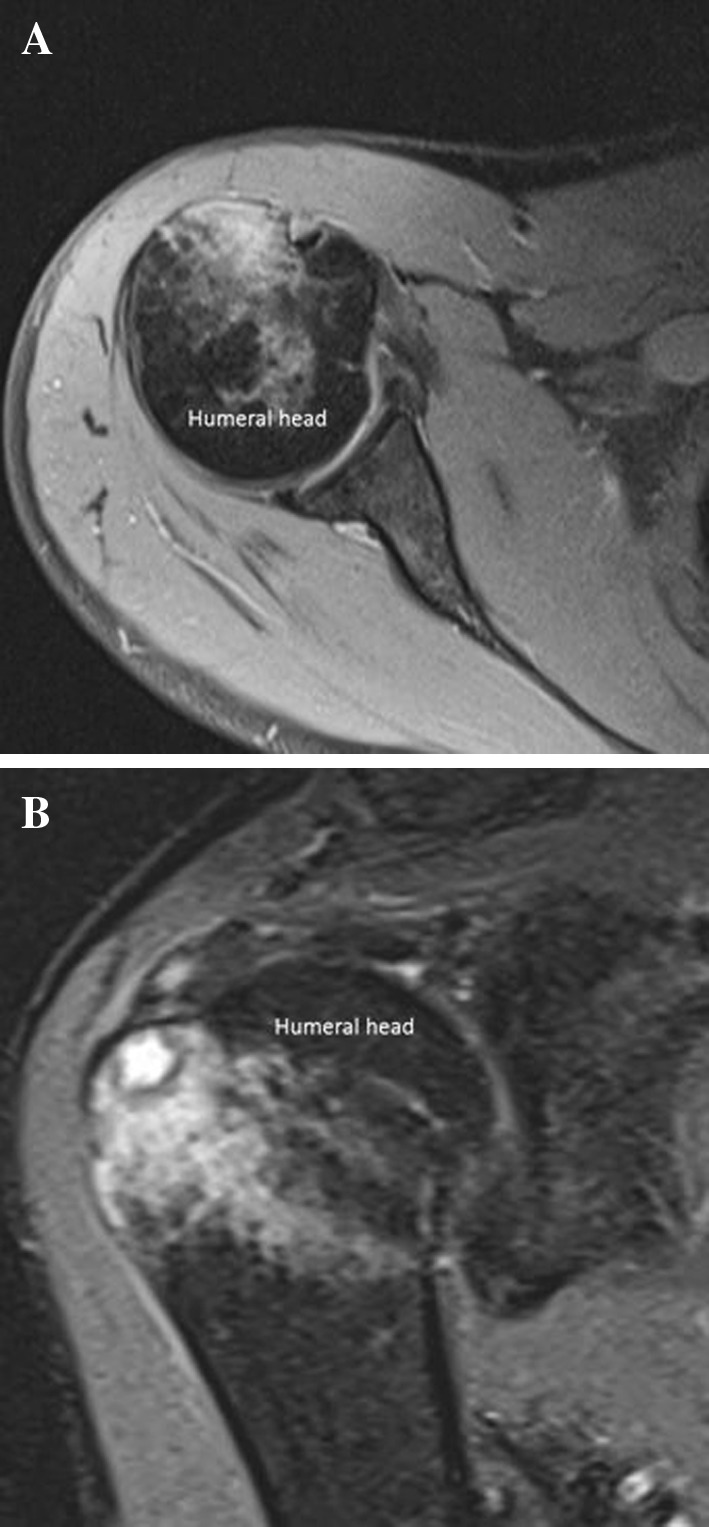

Fig. 6.

Calcium-related osteitis. Axial (a) and sagittal (b) DP-weighted fat suppression sequences show bone marrow edema of the humeral head

Standard radiographs show focal erosions of the humeral head and a rounded sclerotic intraosseous lesion in the greater tuberosity surrounded by a radiolucent halo; if the calcific deposit has migrated outside the humeral head, plain film shows a rounded well-defined lytic lesion in the greater tuberosity, along with a tendon calcification. CT is the gold standard imaging modality to depict bone lesions (Fig. 5); CTI demonstrates cortical erosion of the humeral head and a rounded well-defined lytic area located in the greater tuberosity; it can also detect calcium deposit in its intraosseous location or in the adjacent tendinous insertion. MRI shows a cystic lesion in the greater tuberosity and the intraosseous/intratendinous calcification; MR is superior in evaluating bone medullary involvement, in fact the bone marrow (Fig. 6) surrounding the cystic lesion of the greater tuberosity presents a typical reactive edema pattern extending from the greater to the lesser tuberosity with a characteristic spare of the cranial part of the proximal humeral epiphysis. Both CT and MR can easily depict a possible tendon-associated tear.